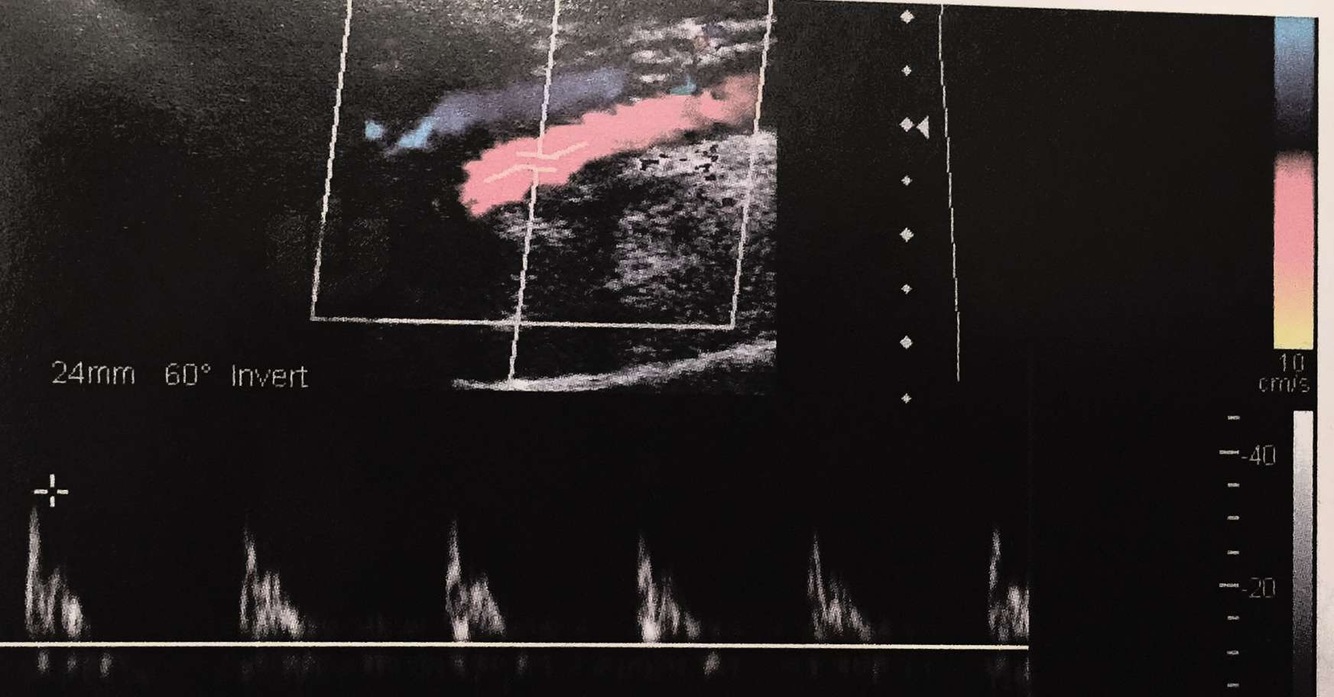

waveform prior to stenosis

peaked -

monophasic -

high resistance

waveform distal to stenosis

parvus et tardus

monophasic

low resistance

hyperemic flow

all above baseline